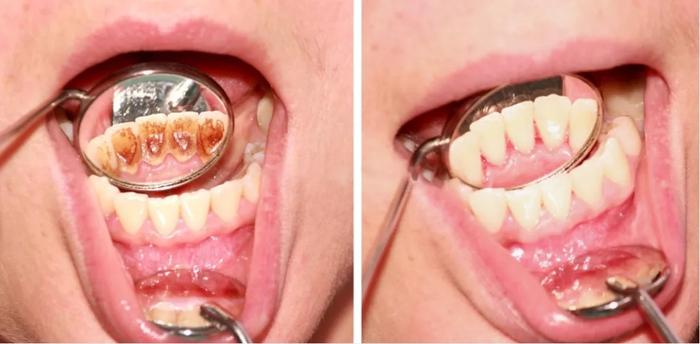

▲牙结石去掉前后的对比图

2.牙龈红肿消退

很多人在洗牙之前牙龈是发炎红肿的,那么原本的牙缝被红肿的牙龈填满,而洗牙过后,口腔卫生状况改善,牙龈不肿了,原本的牙缝就显露了出来,让人感觉上是洗牙造成的牙缝变大。

如果洗牙后你觉得牙缝变大,说明本身就有牙周病,洗牙洗晚了,牙龈不健康,萎缩了,而且牙结石本身就可能会造成牙齿松动,如果尽早采取措施,干掉牙结石,消除炎症,牙齿才会越来越健康。

如不及时除去牙石,牙龈会进一步萎缩,反而会导致牙齿松动脱落。